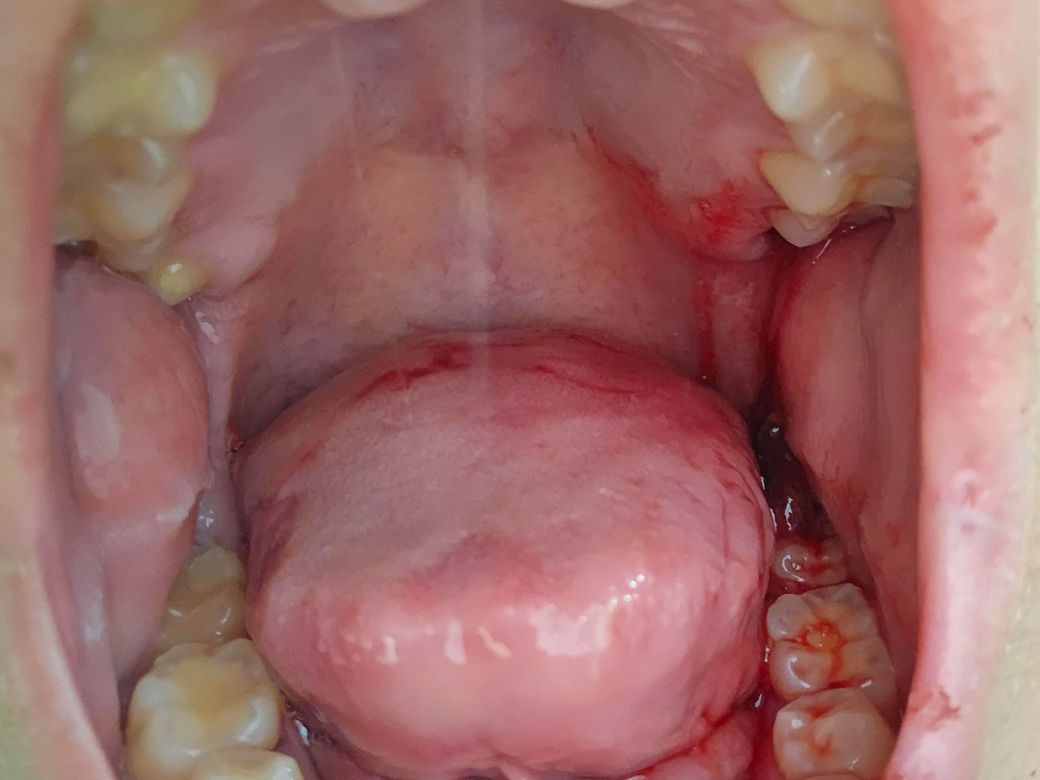

사랑니 발치후 핏덩이가생겼습니다.

사랑니 발치후 2~3시간 동안 거즈물고있다 빼고 침삼키기만하고있었는데 저렇게 핏덩이가 생겻습니다 내비둬도 상관없나요?

오른쪽아랫니입니다.

• 1번 째 사진

사랑니를 발치하고 형성되는 혈병이 너무 커진다면 출혈이 되고 있다는것이기 때문에 거즈를 물어서 지혈을 하는것이 좋습니다.

출혈이 심해서 흐르는 정도라면 거즈를 다시 물어주시고요. 그게 아니라 피떡이 생기는 것은 치유과정에서 자연스러운 것입니다.